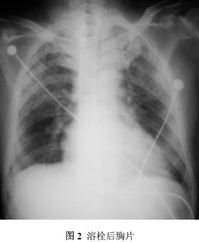

肺部病變表現為肺豐滿脹大,表面有較多出血斑,光鏡下可見肺泡腔內有大量紅細胞及很多含有含鐵血黃素的巨噬細胞,肺泡壁呈局灶性增厚,纖維化,肺泡細胞肥大,電鏡下可見肺泡基底膜增厚及斷裂,內皮下有電子緻密物呈斑點樣沉積,而內皮細胞正常,免疫螢光檢查可見毛細血管壁有IgG,C3呈連續或不連續線樣沉積。